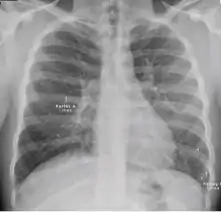

Dense homogenous opacity in right, middle and lower lobe of primary pulmonary TB.